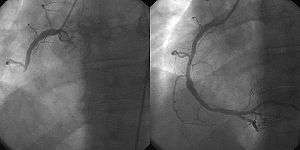

A coronary angiogram (an X-ray with radio-opaque contrast in the coronary arteries) that shows the left coronary circulation. The distal left main coronary artery (LMCA) is in the left upper quadrant of the image. Its main branches (also visible) are the left circumflex artery (LCX), which courses top-to-bottom initially and then toward the centre/bottom, and the left anterior descending (LAD) artery, which courses from left-to-right on the image and then courses down the middle of the image to project underneath of the distal LCX. The LAD, as is usual, has two large diagonal branches, which arise at the centre-top of the image and course toward the centre/right of the image. | |